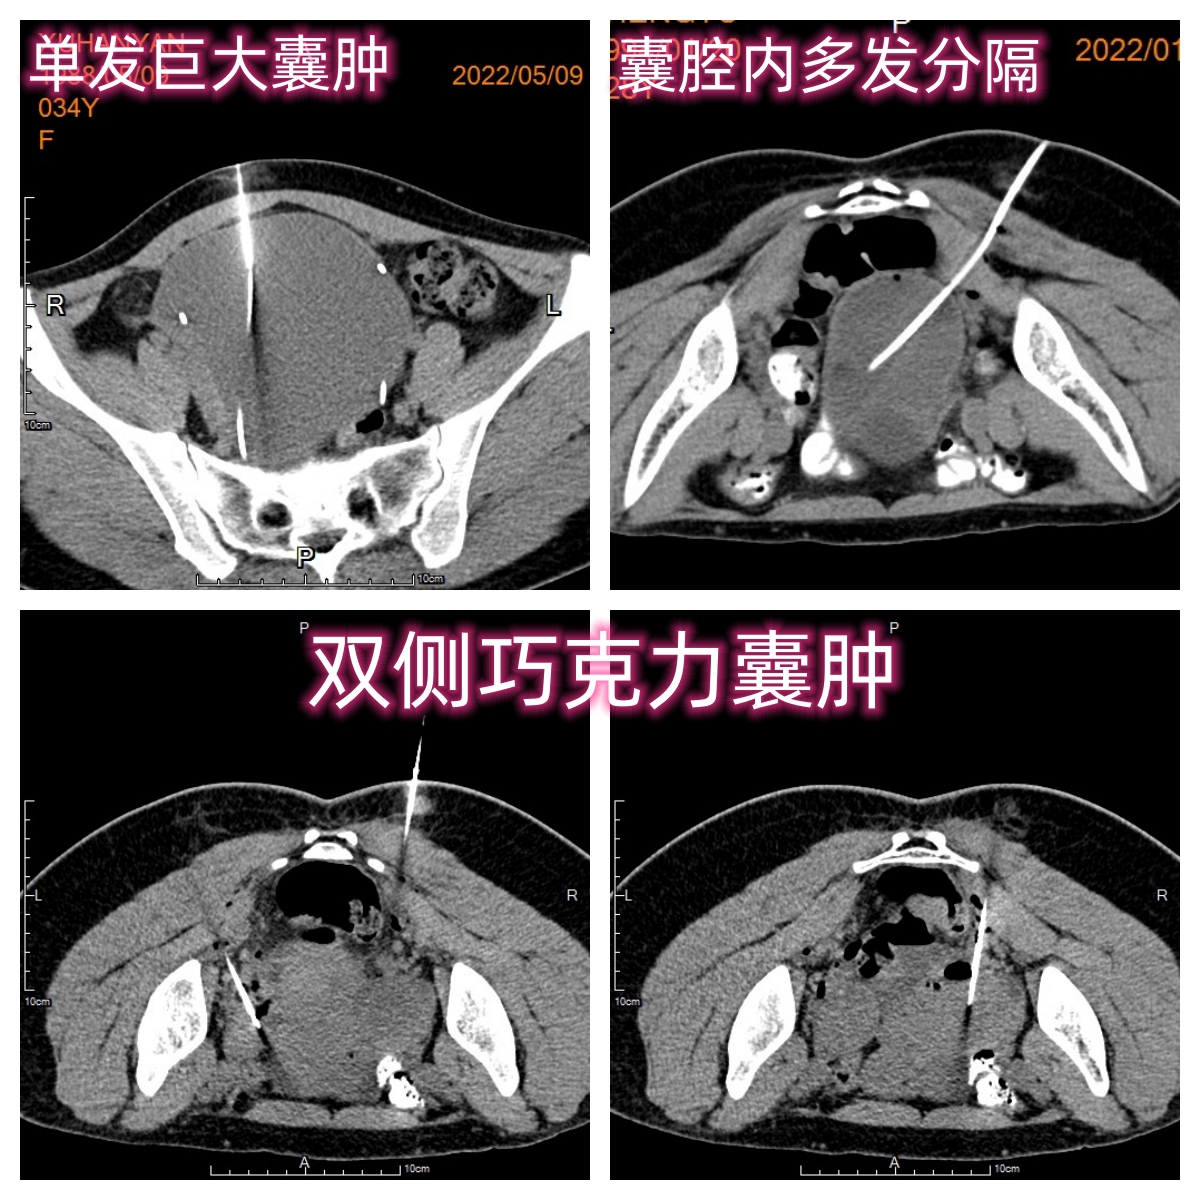

通过改良引导技术及硬化治疗模式,在CT 精准引导下,经皮穿刺留置多侧孔猪尾型引流管,可以更加充分有效抽吸、冲洗囊腔,并可安全、多次注射泡沫硬化剂治疗,更加彻底硬化治疗囊壁,有效粘闭囊壁从而显著提高疗效,同时有效避免囊液及硬化剂外渗风险,显著提高治疗安全性。但该技术的受众人群主要为单个较大囊腔(直径大于4~5cm)的巧克力囊肿患者,对于双侧、多发囊肿,或者囊腔内多发分隔的情况,势必影响囊肿硬化治疗的临床疗效,也使得介入硬化治疗技术仅作为巧克力囊肿的一种补充替代手段之一。CT引导下介入硬化治疗卵巢巧克力囊肿临床研究招募

不同情况下的巧克力囊肿穿刺硬化治疗